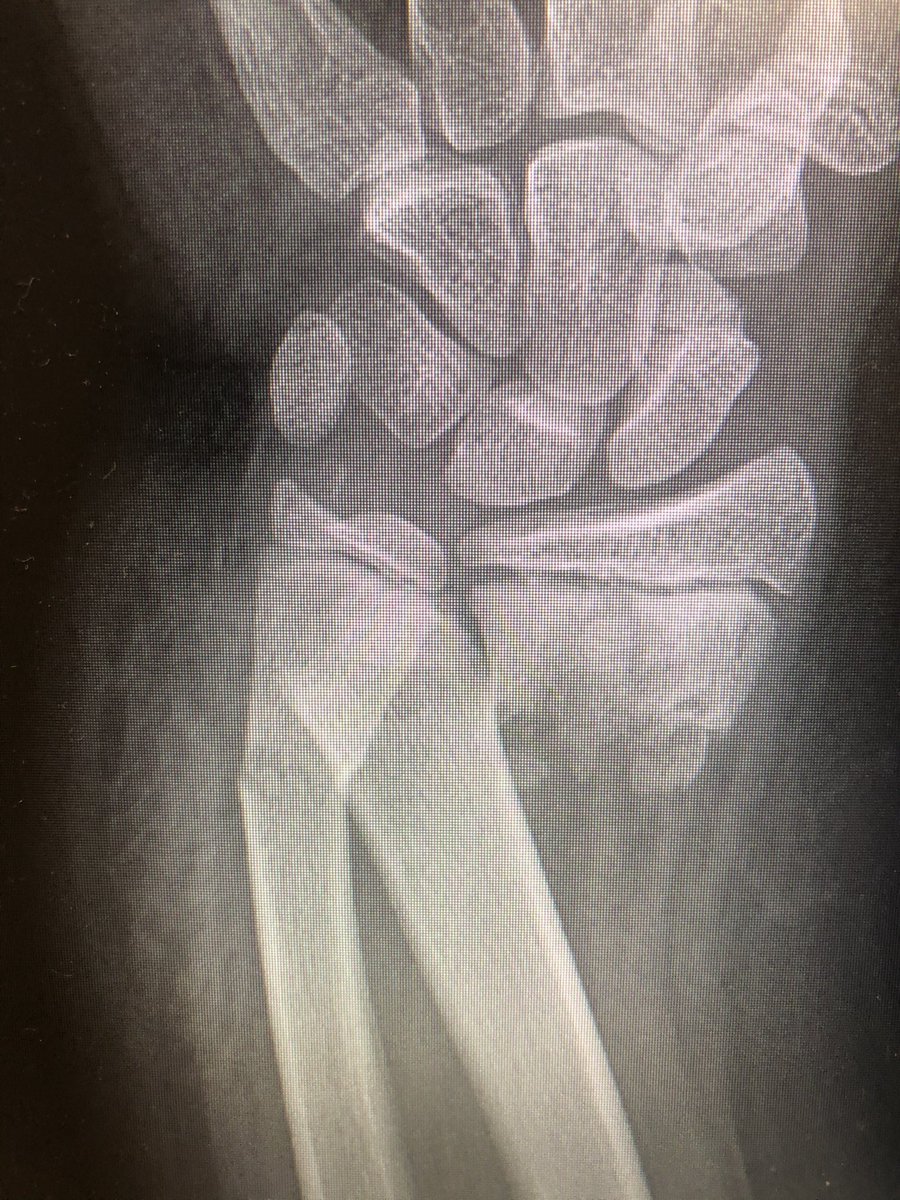

[1/4] Older child with distal both bone forearm with significant coronal plane translation. I thought this would continue to drift radially with time and would not end up looking good in a cast.